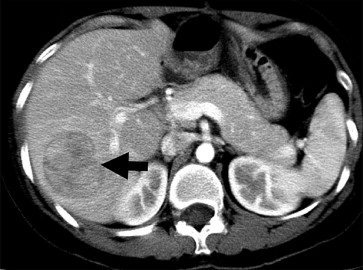

During the following period, the serum α-fetoprotein level was within the normal range. However, a well-defined nodule, 7 mm in size over the lingular segment of the left lung was noted by chest computed tomography 14 months after the previous operation (Fig. 3). Wedge resection of the anterior segment of the left lung was performed. The pathology reported the nodule as metastatic HCC.

Computed tomography showed a well-defined nodule, 7mm in size, over the upper ...

Figure 3.

Computed tomography showed a well-defined nodule, 7 mm in size, over the upper lobe of the left lung (arrow).